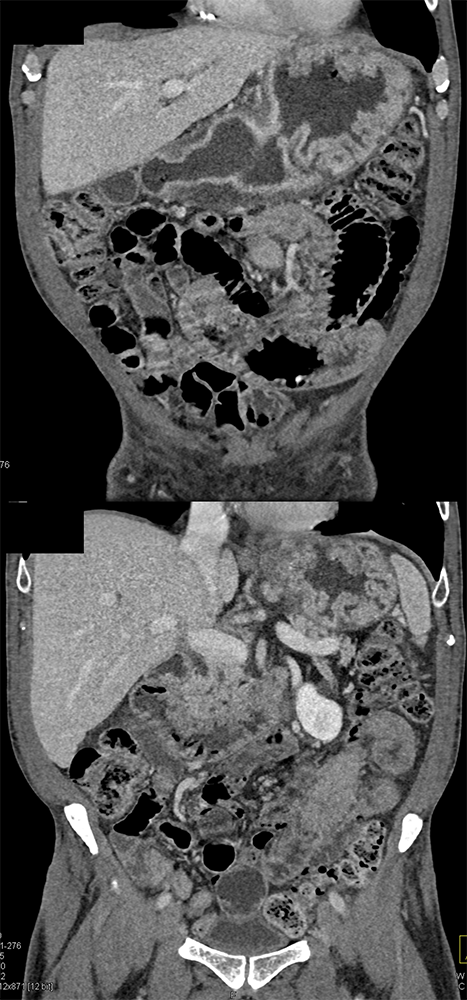

Chemical Gastritis from NSAIDs ![]() |

Abdominal Pain ![]() |

Gastric Ulcer with Perforation ![]() |